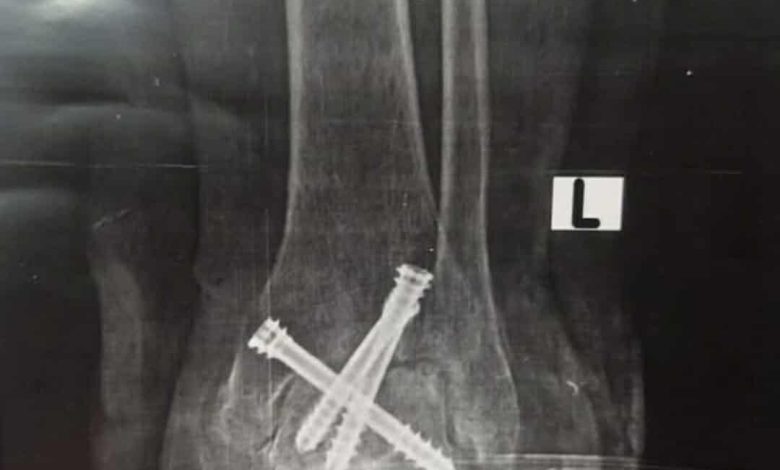

قامت الوحدة بإجراء جراحة لمريض ستيني يعاني من آلام مزمنه وتشوه وتيبس مفصل الكاحل الأيسر وعدم القدرة على المشي بصورة طبيعية حيث تم عمل سمكرة كاملة لمفصل الكاحل لإنهاء معاناة المريض المزمنه عن طريق منظار الكاحل والتدخل الدقيق المحدود والتثبيت بثلاثة مسامير ثنائية الضغط وتمت الجراحة كاملة من خلال جروح بسيطه لا تتعدى واحد سنتيمتر بدون فتح جراحي تقليدي والمريض بصحة جيدة وفي مرحلة التعافي والعلاج